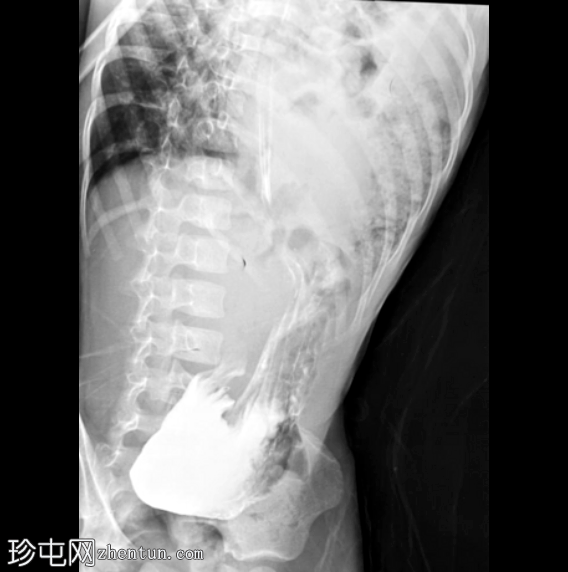

矢状面C+期

动脉期

左侧膈疝通过位于左膈中部的一个缺损形成,伴有纵隔向右侧移位,下方左塌陷。

脾脏、大肠和小肠均有疝气,同时伴有肠系膜上血管疝气。

胃位于下部,靠近主动脉分叉处。

在降结肠和直肠中可见先前荧光透视检查的残留造影剂。